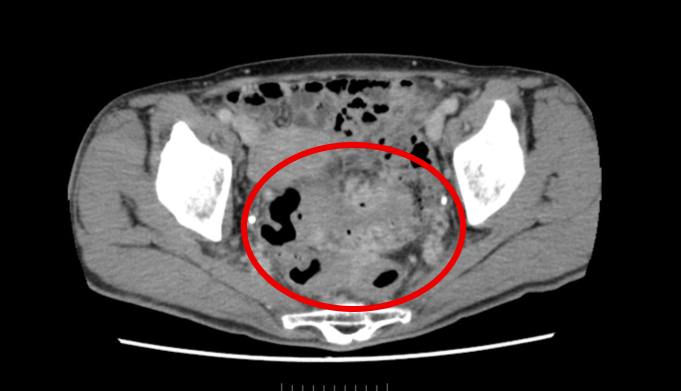

発熱と便通異常で当院へ紹介された50代女性のケースです。

S状結腸という場所にたくさんの泡のような房が見えます。

また、それぞれの腸管の境目がはっきりせず、お互いの癒着していることが予想されます